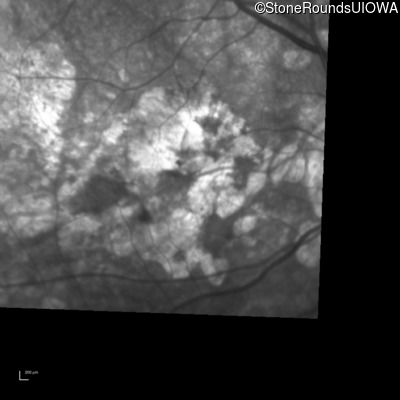

Infrared Fundus Photograph - Left - 20/160 -1

Exemplar